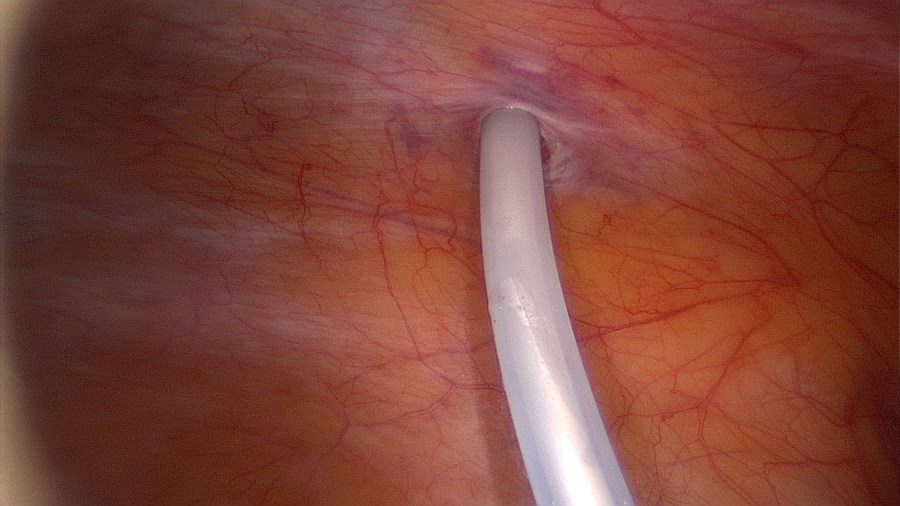

Remove the retriever bag, wash the pelvis, place a drainage (i.e. Robinson 15).